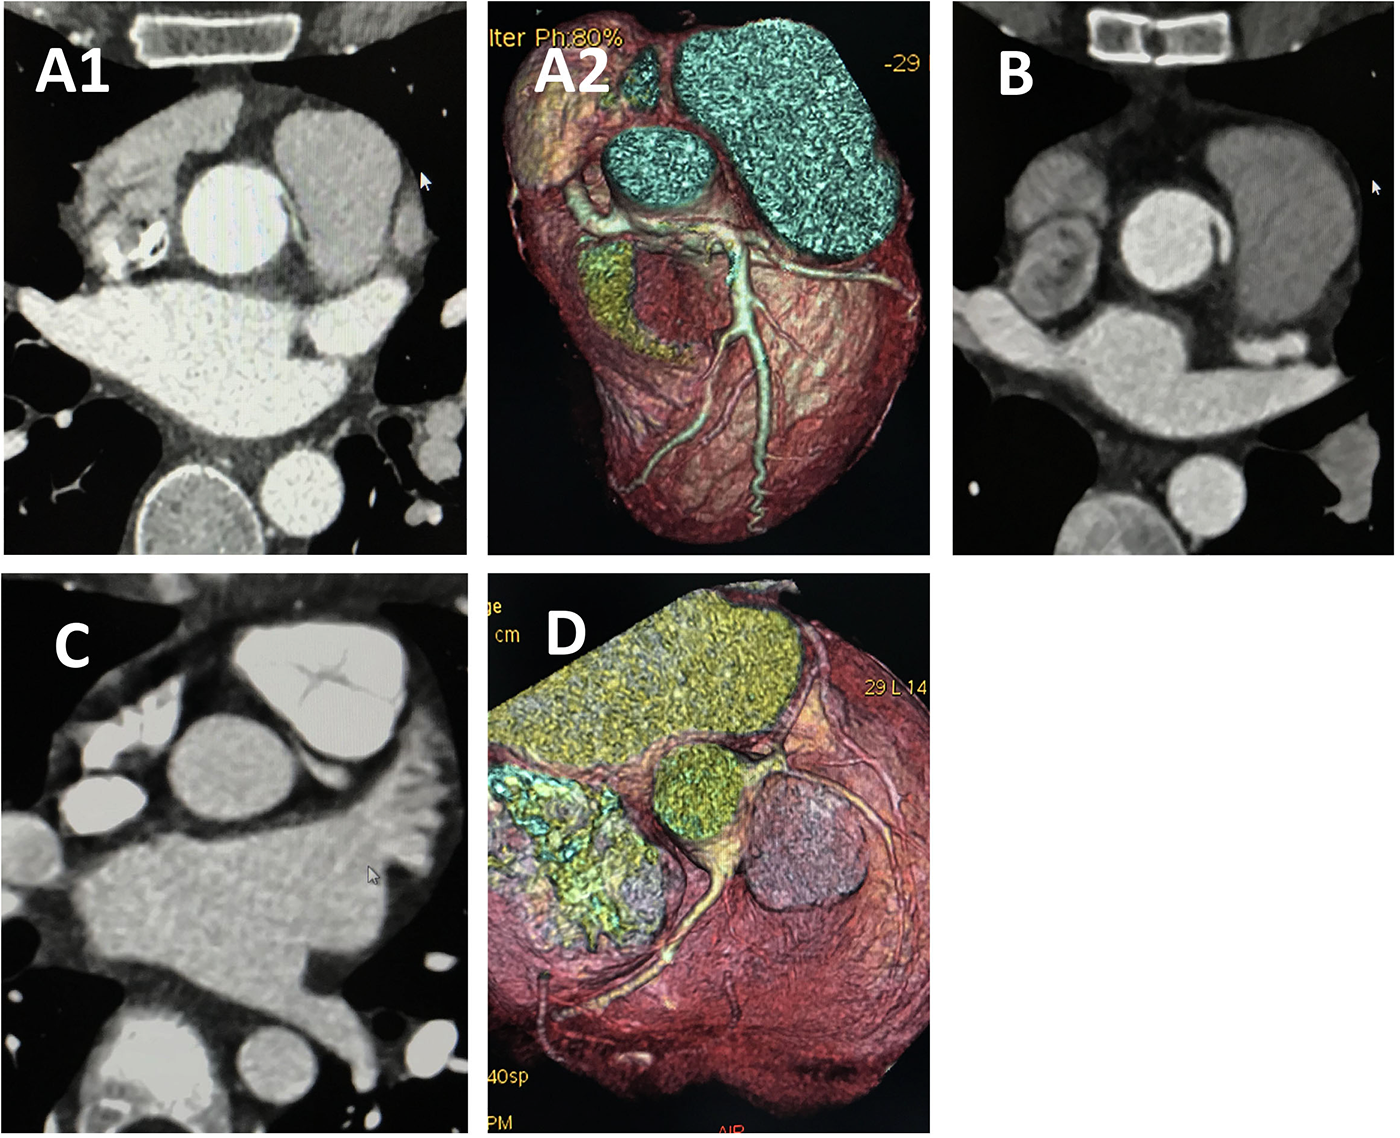

Figure 4

CCTA of case 7 and case 4 underwent angioplasty. Case 7 underwent angioplasty with pulmonary artery patch: (A) Preoperative images showing anomalous left coronary artery arising from the right sinus. (B) Follow-up images showing proximal left main coronary artery without visible stenosis. Case 4 underwent angioplasty with pericardial patch: (C) Preoperative images showing anomalous left coronary artery arising from the right sinus. (D) Follow-up images showing proximal left main coronary artery without visible stenosis. CCTA, coronary computed tomography angiography.